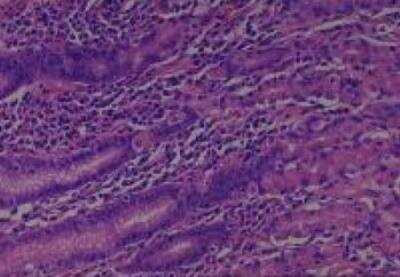

Hematoxylin & Eosin Stain: Human Common Tissue MicroArray (Normal Adjacent) [NBP2-30215] - 102. Stomach